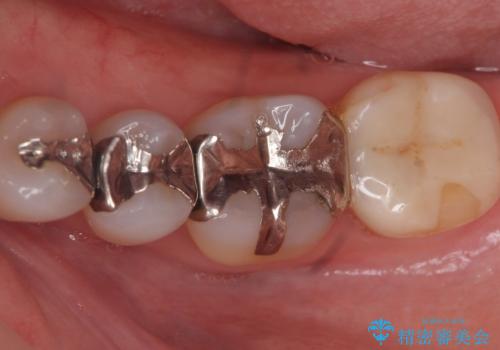

- 矯正前の患者様です。検査により虫歯がありましたのでe-maxインレー治療を行いました。

虫歯がある状態で矯正を始めてしまうと矯正治療中に虫歯が悪化してしまう可能性があります。